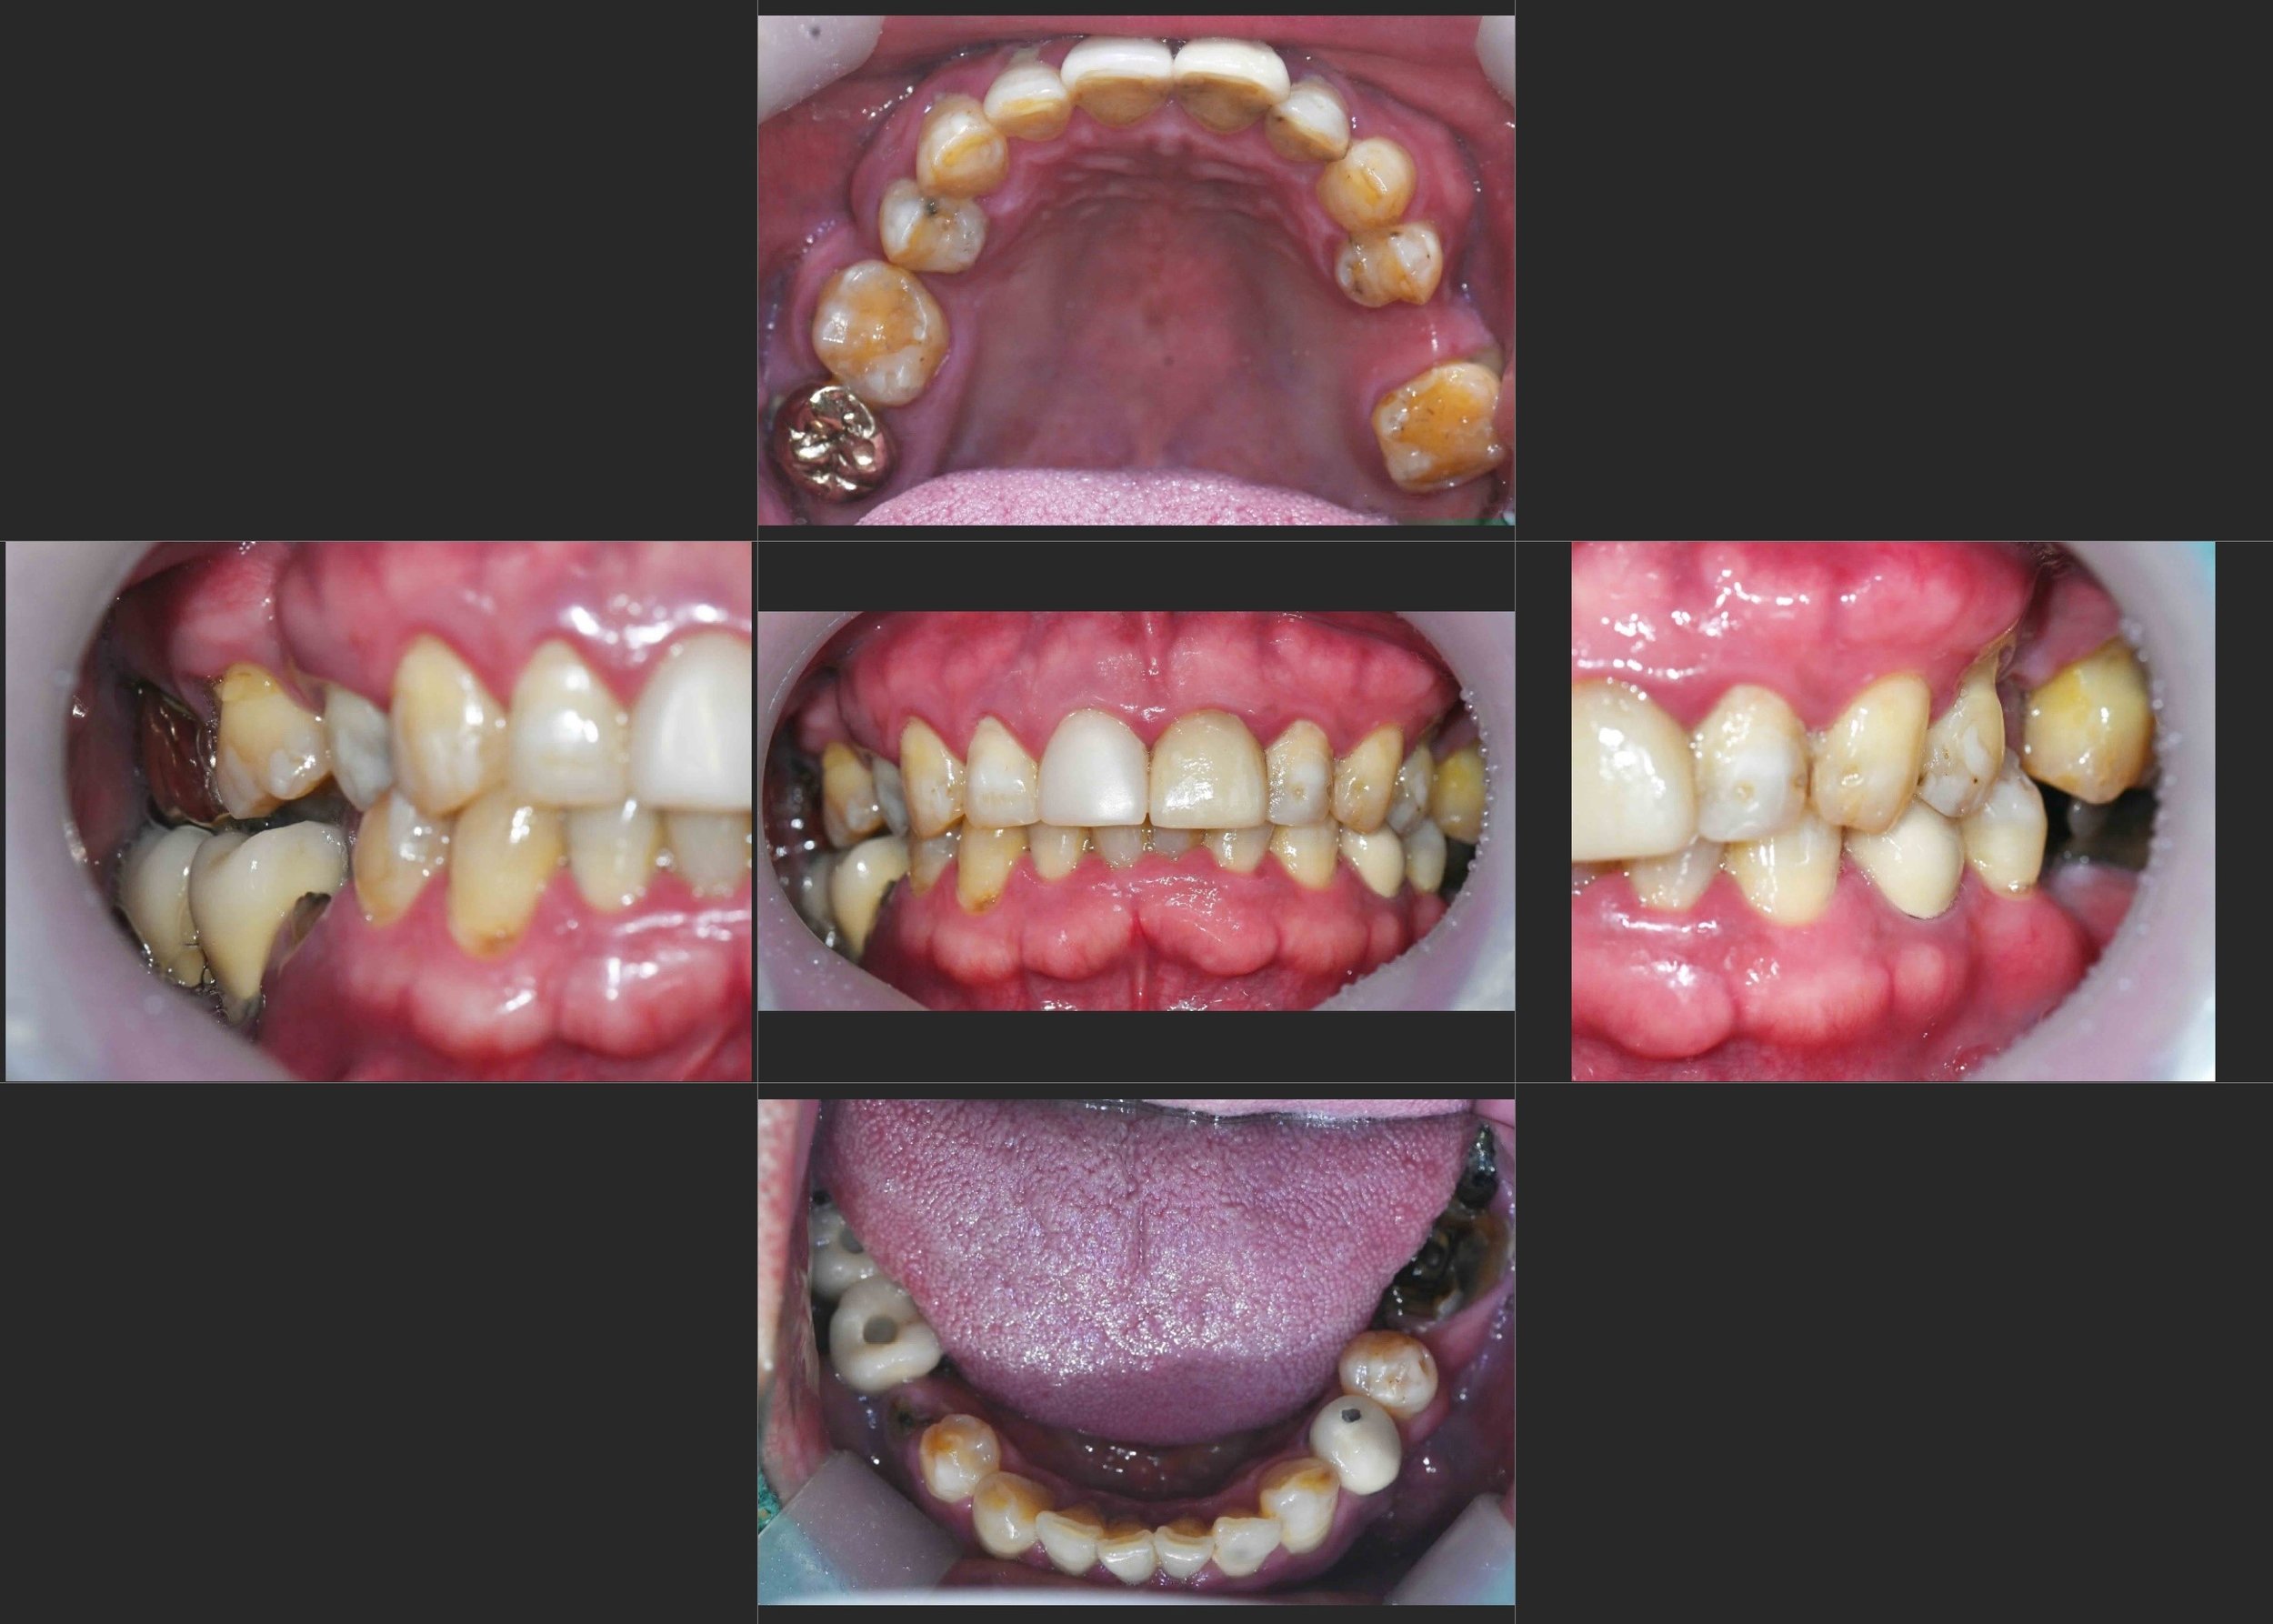

INTRA ORAL - AFTER

4. Final Prosthetic Phasing: Definitive zirconia implant-supported bridges were delivered. Particular attention was paid to creating a harmonious "emergence profile" for maintenance. The final occlusal scheme was designed to be "maintenance-friendly," ensuring easy access for hygiene, vital for patients with a history of severe failures.

The result is a transformative improvement, moving from the discomfort of iatrogenic failure and skeletal collapse to a stable, functional, and symmetrical fixed rehabilitation.